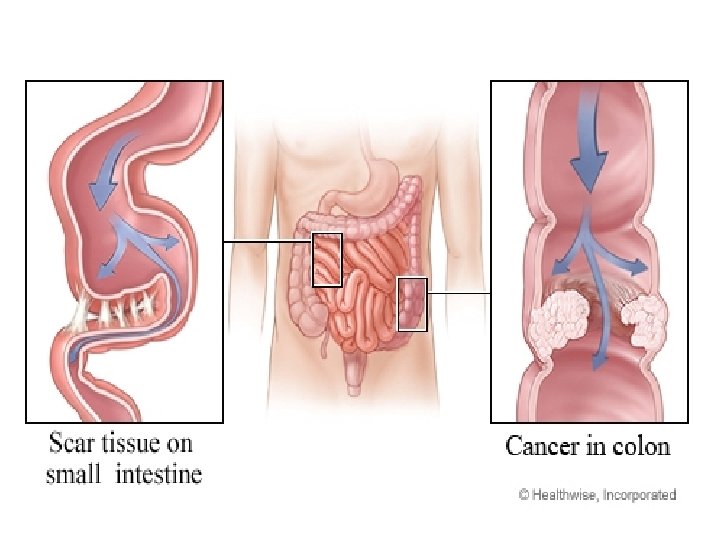

• Okluzioni Intesitnal ( Ileusi) OI eshte mos eliminimi i transitit te materialeve fekale , tretesirave digjestive e te gazrave nga pengesa te ndryshme mekanike ose parelitike.

• Okluzioni mekanik vjen nga patologji qe kane origjinen ne lumenin e zorres, ne murin e saj dhe strukturat indore fqinje. • Okluzioni intestinal nga strangulacioni shoqerohet edhe me bllokimi te menjehershem te eneve te gjakut dhe me nderprerjen e qarkullimit te gjakut.

• Okluzioni intestinal pasohet nga zgjerimi i segmentit te zorres (mbi pengese), tensionim dhe hollim te murit te saj. • Nderlikohet dhe perkeqsohet edhe qarkullimi I gjakut (venoz, kapilarve arterial) e deri ne paraliza te zorres me crregullime te permeabilitetit te murit te zorreve --crregullim te perthithjes se lengjeve dhe kriprave---duke krijuar substanca te panevojshme dhe te demshme per organizmin

• Inflamacioni i apendiksit ndodh pas bllokimit te pjesshem/te plote te lumenit te apendiksit nga masa fekaloide, masa parazitare, trupa te huaj, tm.